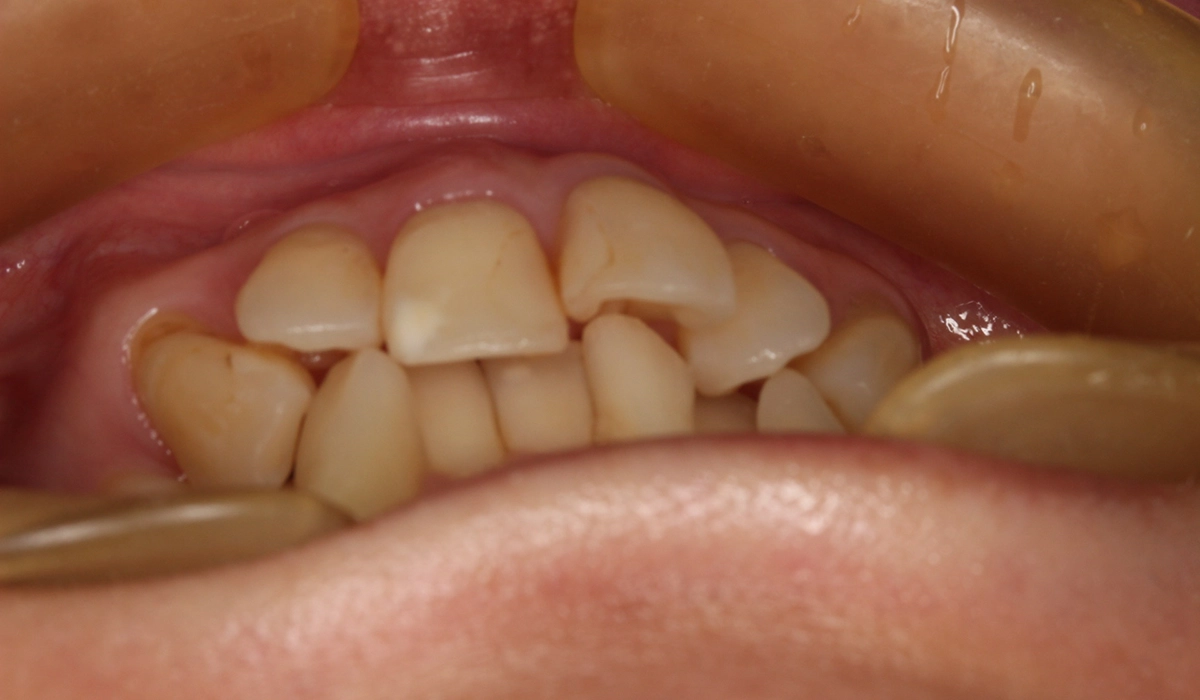

術前:前歯部

術前:オーバージェット